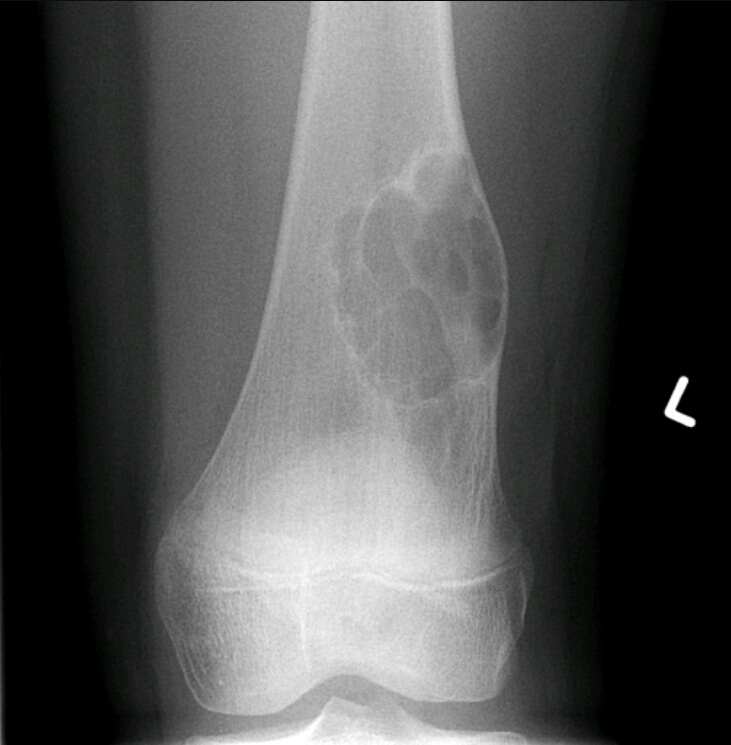

Multiple Osseous stalks of the tibia, fibula and femur

Hereditary multiple exostosis

Findings? Diagnosis?

Impaired bone growth, short ulna, bowing of radius, subluxation of the radioulnar joint

Madelung deformity